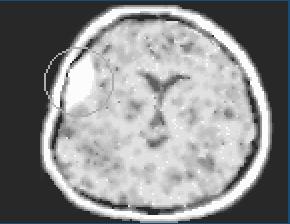

Biela výplň na kraji lepky značí subdurálny hematón, alebo krvácanie do mozgu.